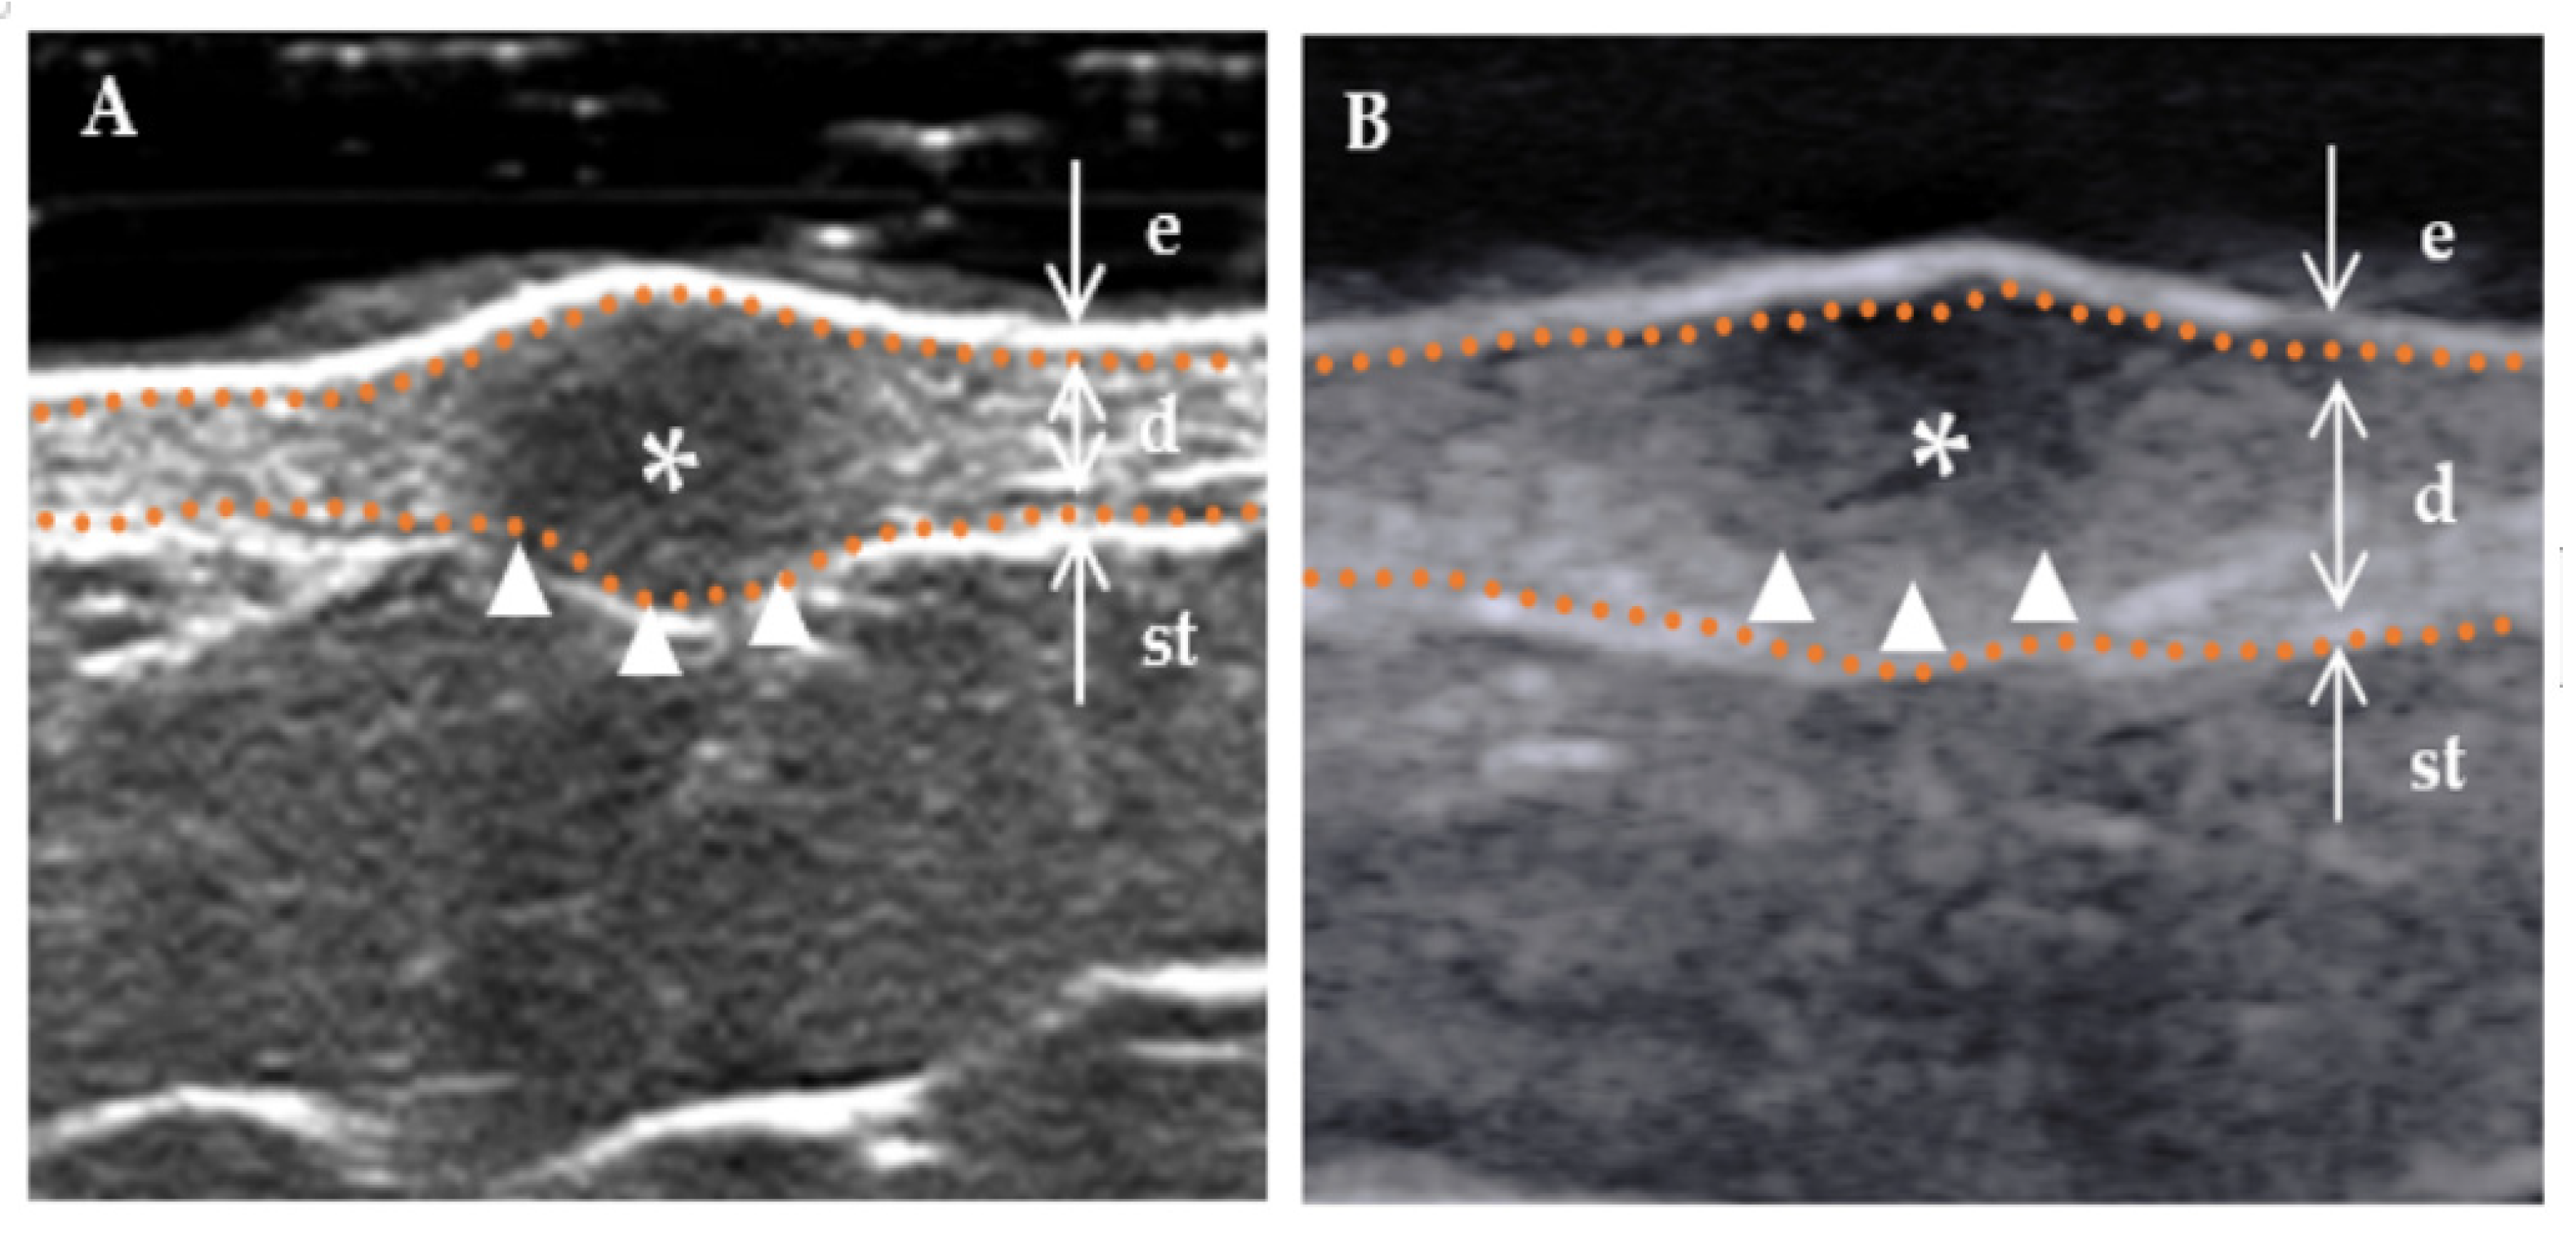

Figure 2.

Boundary of a DF lesion. * Indicates the precise location of the lesion on the ultrasound image. The skin layers are indicated by dotted orange lines, with arrows indicating a hyperechoic epidermis (e), an isoechoic dermis (d), and a subcutaneous tissue (st). The boundary of the lesion (indicated by a white triangle) is distinctly demarcated. (A) “Regular” lesions are characterized by smooth edges without infiltration into the adjacent tissue. (B) “Irregular” lesions are characterized by jagged edges that can penetrate the surrounding dermis or subcutaneous tissue.